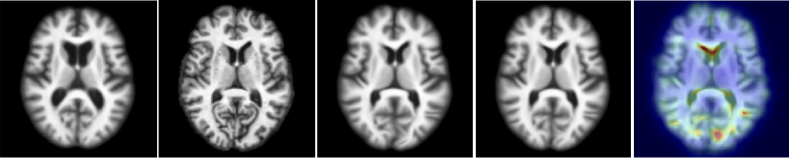

Figure 2: Test example for 2D (top) and 3D (bottom). From left to right: moving (atlas) image, target image, deformation result by optimizing LDDMM energy, deformation result using 50 samples from probabilistic network with a stride of 14 and patch pruning, and uncertainty as square root of the sum of the variances of deformation in all directions mapped on the predicted registration result. The colors indicates the amount of uncertainty (red = high uncertainty, blue = low uncertainty). Best viewed in color.

2D Data. For the 2D experiment, we compare our method with semi-coupled dictionary learning (SCDL), which was used to predict initial momenta for LDDMM in [2]. To compare the deformation prediction accuracy using different parameterizations, we trained (i) networks predicting the initial velocity, v0=Km0subscript𝑣0𝐾subscript𝑚0v_{0}=Km_{0}, and the displacement field, Φ(1)idΦ1id\Phi(1)-\operatorname{id}, of LDDMM, respectively. For the initial momentum and the initial velocity parameterizations, the resulting deformation map Φ(1)Φ1\Phi(1) was computed by integrating Eqs. (2). We quantify the deformation errors as the pixel-wise 2-norm of the deformation error with respect to the ground-truth deformation obtained by PyCA LDDMM. Table 1 shows the error percentiles over all pixel and test cases. We observe that our initial momentum networks significantly outperform SCDL and also improve prediction accuracy compared to the initial velocity and the displacement parameterizations in both the 1-stride and the 14-stride ++ patch pruning cases. In contrast to the initial velocity and the displacement parameterizations, both our deterministic and our probabilistic networks show comparatively small sensitivity to patch pruning and stride, validating our hypothesis that the momentum-based LDDMM parameterization is well-suited for fast predictive image registration. One of the hallmarks of LDDMM registration is that given a sufficiently strong regularization, the obtained deformation maps, Φ(1)Φ1\Phi(1), will be diffeomorphic. To assess this property, we computed the local Jacobians of the deformation maps. Assuming no coordinate system flips, a diffeomorphic Φ(1)Φ1\Phi(1) should have a positive definite Jacobian everywhere, otherwise undesirable foldings exist. Column ‘detJ>0det𝐽0\text{{det}}J>0’ of Table 1 lists the percentage of test cases with positive definite Jacobian, revealing that our initial-momentum based networks retain this property in all scenarios, even for very large strides and patch pruning. Direct displacement prediction, however, cannot even guarantee diffeomorphic transformations for a stride of 1 (which includes a lot of local averaging) for all our test cases and results in no diffeomorphic transformations at a stride of 14. Velocity prediction performs slightly better, but can also not guarantee diffeomorphic maps at large strides. Similarly to existing optical flow prediction methods [16, 4], a direct prediction of displacements or velocities cannot encode smoothness assumptions or enforce transformation guarantees. Our momentum parameterization encodes these assumptions by design. Fig. 2 shows an example of our 2D deformation prediction with uncertainty. The predicted deformation is close to the one generated by costly LDDMM optimization. The uncertainty map shows high uncertainty at the anterior edge of the ventricle and the posterior brain cortex where drastic shape changes occur, which can be seen in the moving and the target image.

3D Data. Similar to the 2D case, we computed the deformation error for every voxel in all test cases; results are listed in Table 1. Our networks achieve sub-voxel accuracy for about 99.8% of all the voxels. Fig. 2 shows one 3D registration result using the predicted deformation from our probabilistic 3D network using the mean of 50 initial momentum samples, as well as the uncertainty of the deformation field. Our prediction is able to handle large deformations. As in 2D, the uncertainty map highlights areas with drastic and ambiguous deformations.